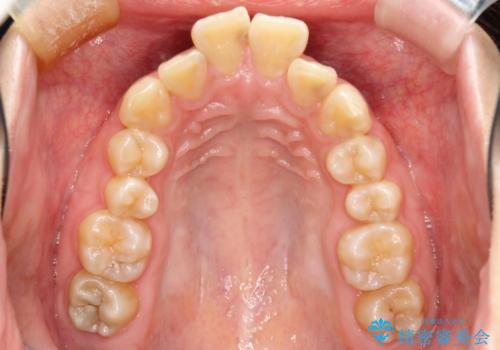

- 口元の閉じにくさと、前歯のでこぼこの歯並びを気にして来院された患者様です。

口元を積極的に引っ込めるために、上下左右の小臼歯計4本を抜歯することとしました。

咬み合わせが深く、咬合力強いため、補助装置を使用しながら積極的に口元を下げることとしました。